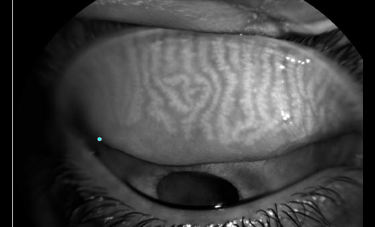

המחקר עסק בסוגיה עליה עדיין אין תשובה חד משמעית והיא האם יש קשר בין הרכבת עדשות מגע לבין בעיה בבלוטות המבומיאן MGD. בדקנו האם יש הבדל בחומרת MGD בין קבוצת מרכיבי עדשות מגע לבין קבוצת נבדקים שאינם מרכיבים עדשות ובחנו את הדירוג בעזרת שיטות אובייקטיביות וסובייקטיביות.